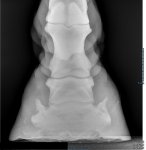

Any one had similar issues with happy field sound result..( My Ex driving horses) current owner is devastated, Vet says we have to wait and see, not field sound at moment, this all happened in last 6 weeks. If he is not field sound to retire, then the other option is PTS ..He is ID x Gypsy Va, 17h, age 18.

One Bute a day at moment. Not insured now. We have between us, owned him 11 years